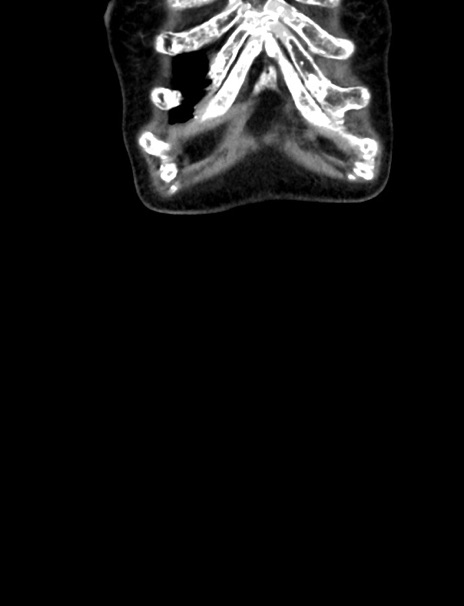

横断像